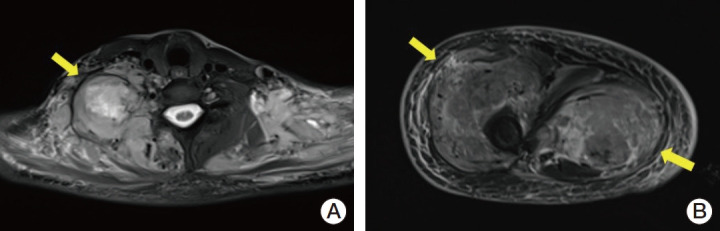

Inflammatory myofibroblastic tumor (IMT) is a rare entity, primarily affecting young individuals, often involving the abdomen, pelvis, or lung. Approximately 50% of IMTs harbor anaplastic lymphoma kinase (ALK) gene rearrangements, making ALK inhibitors a viable treatment. We report a case of a 40-year-old female with metastatic IMT harboring a CARS1-ALK fusion. Initial chemotherapy failed, but targeted therapy with alectinib through the KOrean Precision Medicine Networking Group Study of MOlecular profiling guided therapy based on genomic alterations in advanced Solid tumors (KOSMOS)-II study led to significant tumor regression and ongoing, durable clinical improvement of 19 months. This case highlights the importance of precision medicine and raises the reappraisal of targeted agents outside of approved indications for rare cancers with actionable genomic alterations.